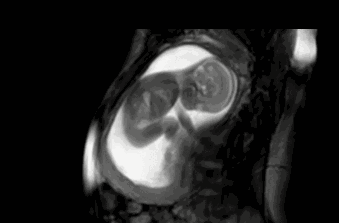

三个月的时候,宝宝还不很调皮,宝妈几乎感觉不出来怀孕,肚子也不明显隆起,我们看看宝宝在宝妈肚子里是什么状态呢?图片说明宝宝是正着呆在宝妈肚子里,由于很小,骨骼大脑等也都没有发育完成,所以宝宝很安静。

六个月的时候,宝宝已经都发育出来,只不过还没有“长结实”,这个时候的宝宝体重大概有650克左右,身高也有了30厘米,倒立着在肚子里,但是并不影响宝宝的调皮,宝宝会偶尔在宝妈肚子里闹一闹,这个时候宝妈就会感受明显,也就是胎动,宝妈可以有意识的记录宝宝的胎动了。